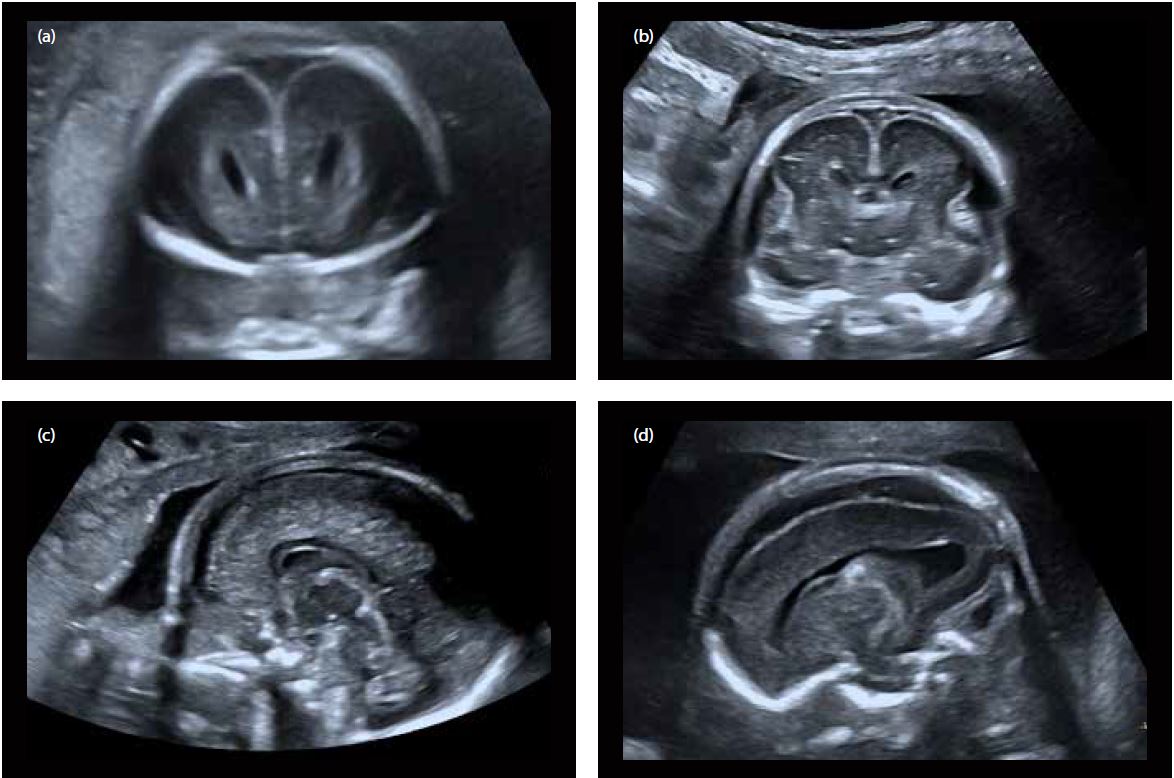

Візуалізація: у B-режимі структури головного мозку плоду 19-21 тижня були проаналізовані з високою впевненістю оператора в діагностиці завдяки дуже високій якості зображення, яке забезпечує датчик. Структури головного мозку, отримані в окремих площинах сканування, представлені з чудовою роздільною здатністю та контрастністю та оптимальним співвідношенням сигнал/шум (мал. 1).

Малюнок 1 Мозок плоду 19-20 тиждень гістаційного віку:

a) та b) Фронтальна площина

c) Серединний сагітальний скан з візуалізацією мозолистого тіла та черв’яка мозочка

d) Косий парасагітальний зріз (візуалізація бічного шлуночка, судинного сплетення та паренхіми головного мозку